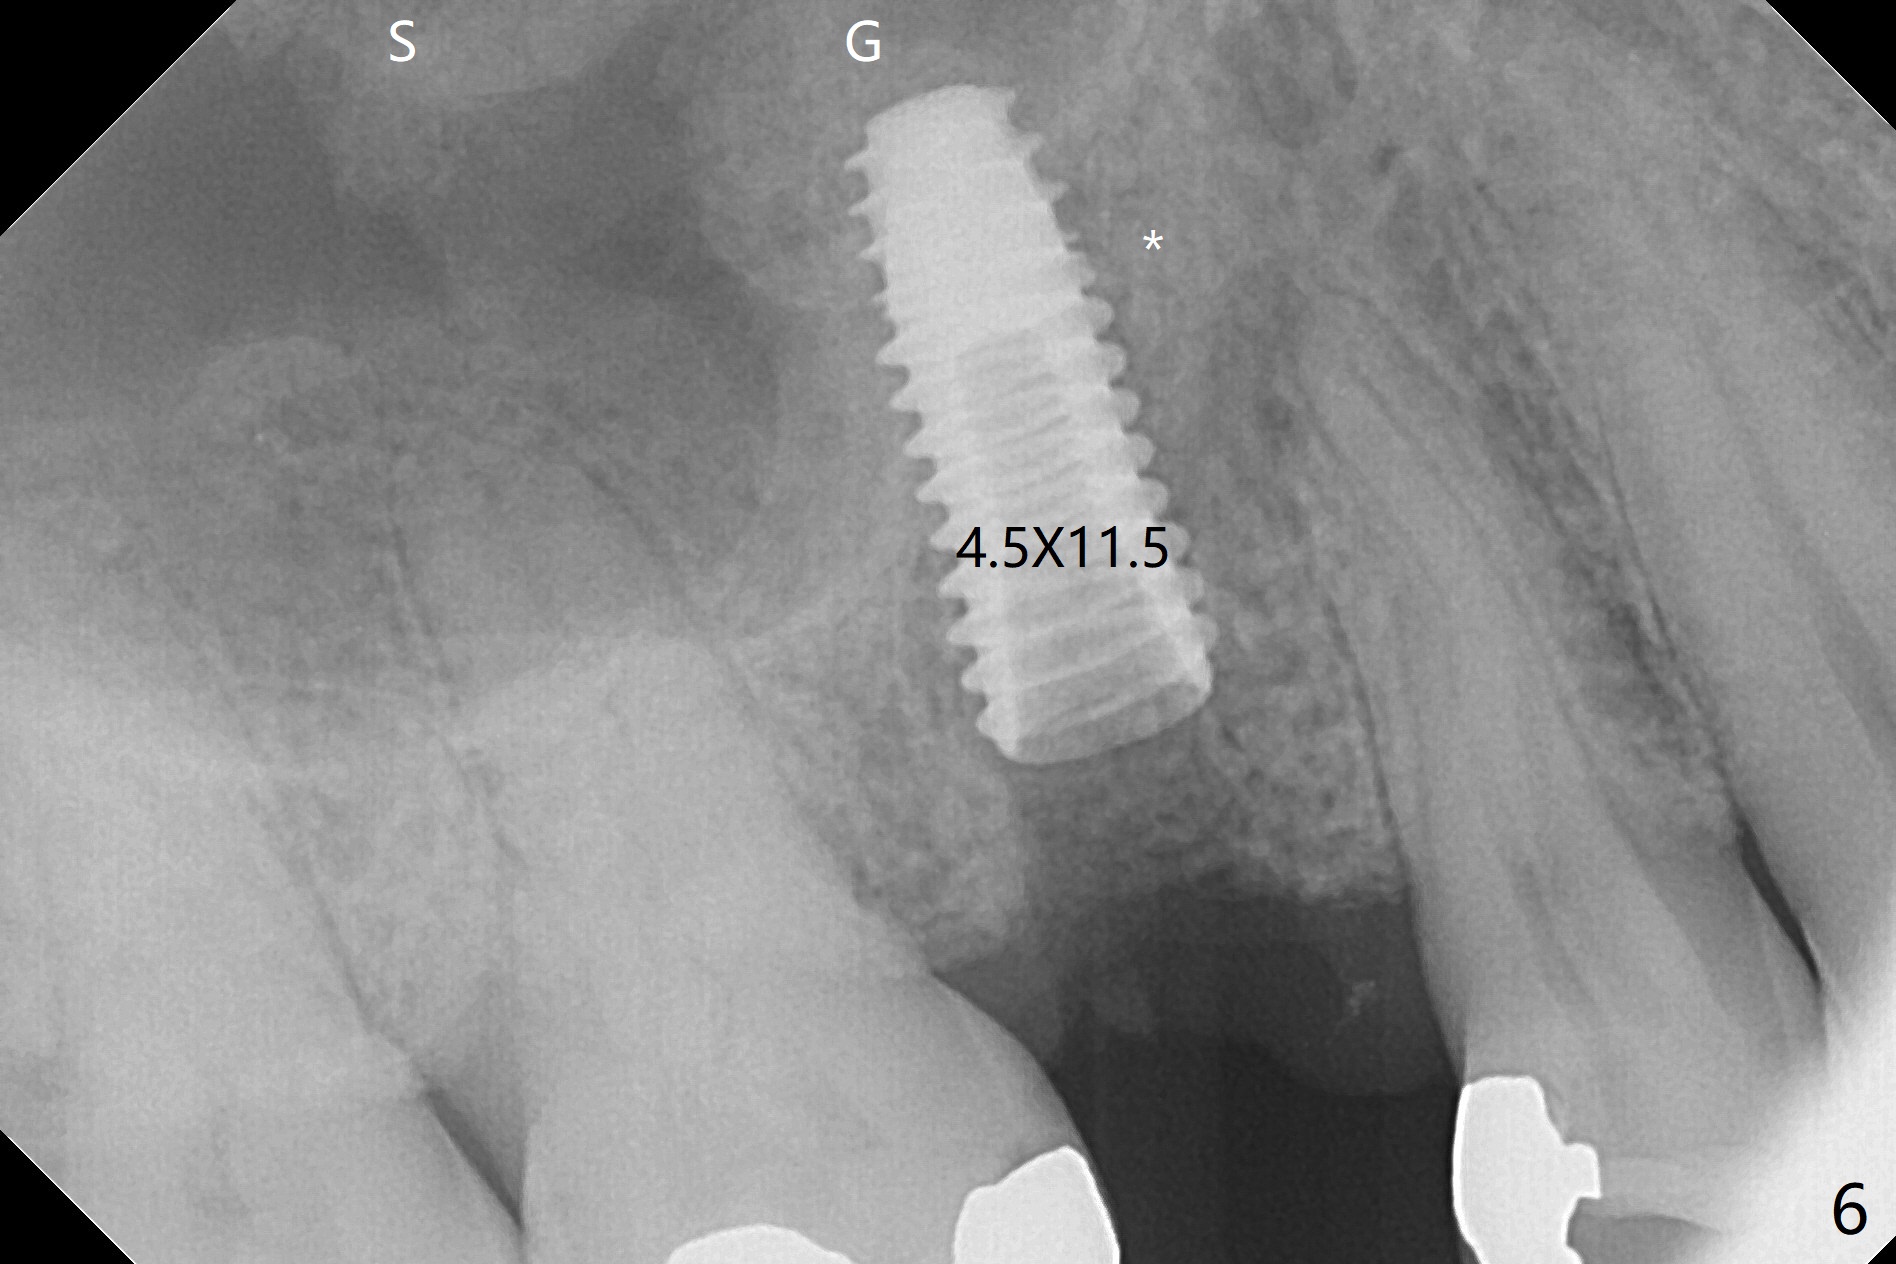

The 48-year-old man agrees to extract the tooth #4 with buccal and palatal fistulae (Fig.1,2 >) and large PARL (Fig.3 *) because of purulent discharge. The large post (Fig.3 P) is most likely associated with a longitudinal fracture. The latter is not noted until postop (Fig.4 <). Intraop finding is large amount of granulation tissue removed from the mesial apical region (Fig.3,5 *). With 10.5 mm offset, Sinus Approach Drill (19 mm) is estimated too short for sinus lift after 3x8.5 mm drill. Without careful repeated check, 2.2x10 and 2.2x11.5 mm drills are used. The sinus floor is perforated, but the membrane seems to be intact. The perforation is too small to insert PRF, but alright for allograft. Then nose blowing test shows that the sinus membrane is perforated, which seems to be repaired after placement of 2 pieces of PRF membrane, followed by another round of allograft (Fig.5 G), which is lifted by a 4x10 mm IS dummy implant. Before placement of a 4.5x11.5 mm final UF implant, allograft is placed in the 3 defective bony areas mentioned above, including the apical mesial one (Fig.6 *). But the final UF implant seems too short with non-satisfactory torque. The latter appears to be solved with the increased length of the implant (Fig.7). The gingiva around the provisional (P) is healthy without fistulae buccal (Fig.8) or palatal 17 days postop (Fig.9). A new abutment with 1 mm longer cuff is seated completely 5.5 months postop (Fig.10 < (no gap), as compared to Fig.7). The lower portion of the mesial defect seems to have been repaired (Fig.11 arrow, as compared to Fig.7). The bone in the sinus seems stable 1.5 years postop (Fig.12). There is no crestal bone loss 4 months post cementation (Fig.13). Return to Upper Premolar Immediate Implant, Trajectory II Xin Wei, DDS, PhD, MS 1st edition 09/27/2019, last revision 04/12/2021